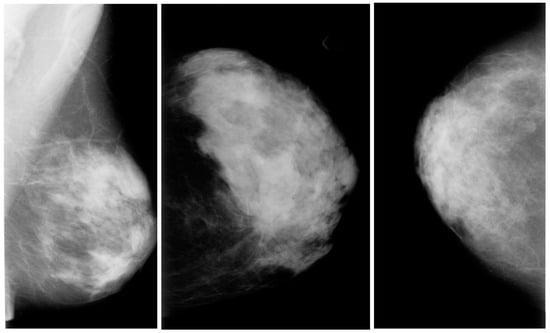

3.1. Mammography Images

Mammography Datasets

- The digital database for screening mammography (DDSM) comprises 2620 mammograms scanned from film which were then separated into 43 volumes (Figure 3). For each example, there are four breast mammograms since the Mediolateral Oblique (MLO) and Cranio-Caudal projections were used to photograph each breast side. The dataset includes pixel-level annotations for the suspicious regions and the ground truth. The breast density score for each patient was calculated using the ACR BI-RADS (American College of Radiology Breast Imaging Reporting and Data System). The file for each case also contains information about the size and resolution of each scanned image. JPEG (Joint Photographic Experts Group) format, available in various formats and resolutions, was used for the images.

- The Curated Breast Imaging Subset of the DDSM (CBIS-DDSM) is an upgraded version of the DDSM that includes bounding boxes for the region of interest (ROI), updated mass segmentation, and decompressed pictures. The data were picked and reviewed by mammographers with the necessary training, and the images are in the Digital Imaging and Communication in Medicine (DICOM) format. The collection is 163.6 GB in size and contains 6775 studies. There were 10,239 images in total, all mammography scans with associated mask images. CSV files are associated with the dataset that includes the patients’ pathological data. A mass training set, a mass testing set, a training set for calcification, and a testing set for calcification make up the dataset’s four CSV files. The mass testing set only includes images for 378 cancers, whereas the dataset consists of images of 1318 tumors. Images for 1622 calcifications are included in the calcification training set, whereas photos for 326 calcifications are included in the calcification testing set.

- IN Breast: Breast consists of 410 images and 115 cases. In 90 of the 115 cases, there was malignancy in both breasts. The dataset represents the four types of breast illnesses: breast bulk, breast calcification, breast asymmetries, and breast distortions. Images of (CC) and (MLO) views, stored in DICOM format, are included in the dataset. The dataset also offers the breast density score from the Breast Imaging-Reporting and Data System (BI-RADS).

- Mini-MIAS: The dataset includes ground truth indicators for potential abnormalities and 322 digital films. The collection contains five types of abnormalities: masses, architectural distortion, asymmetry, and normal. Ultimately, 1024 by 1024 pixels) were used as the final resolution for the images. The images are accessible to everyone on the University of Essex’s Pilot European Image Processing Archive (PEIPA).